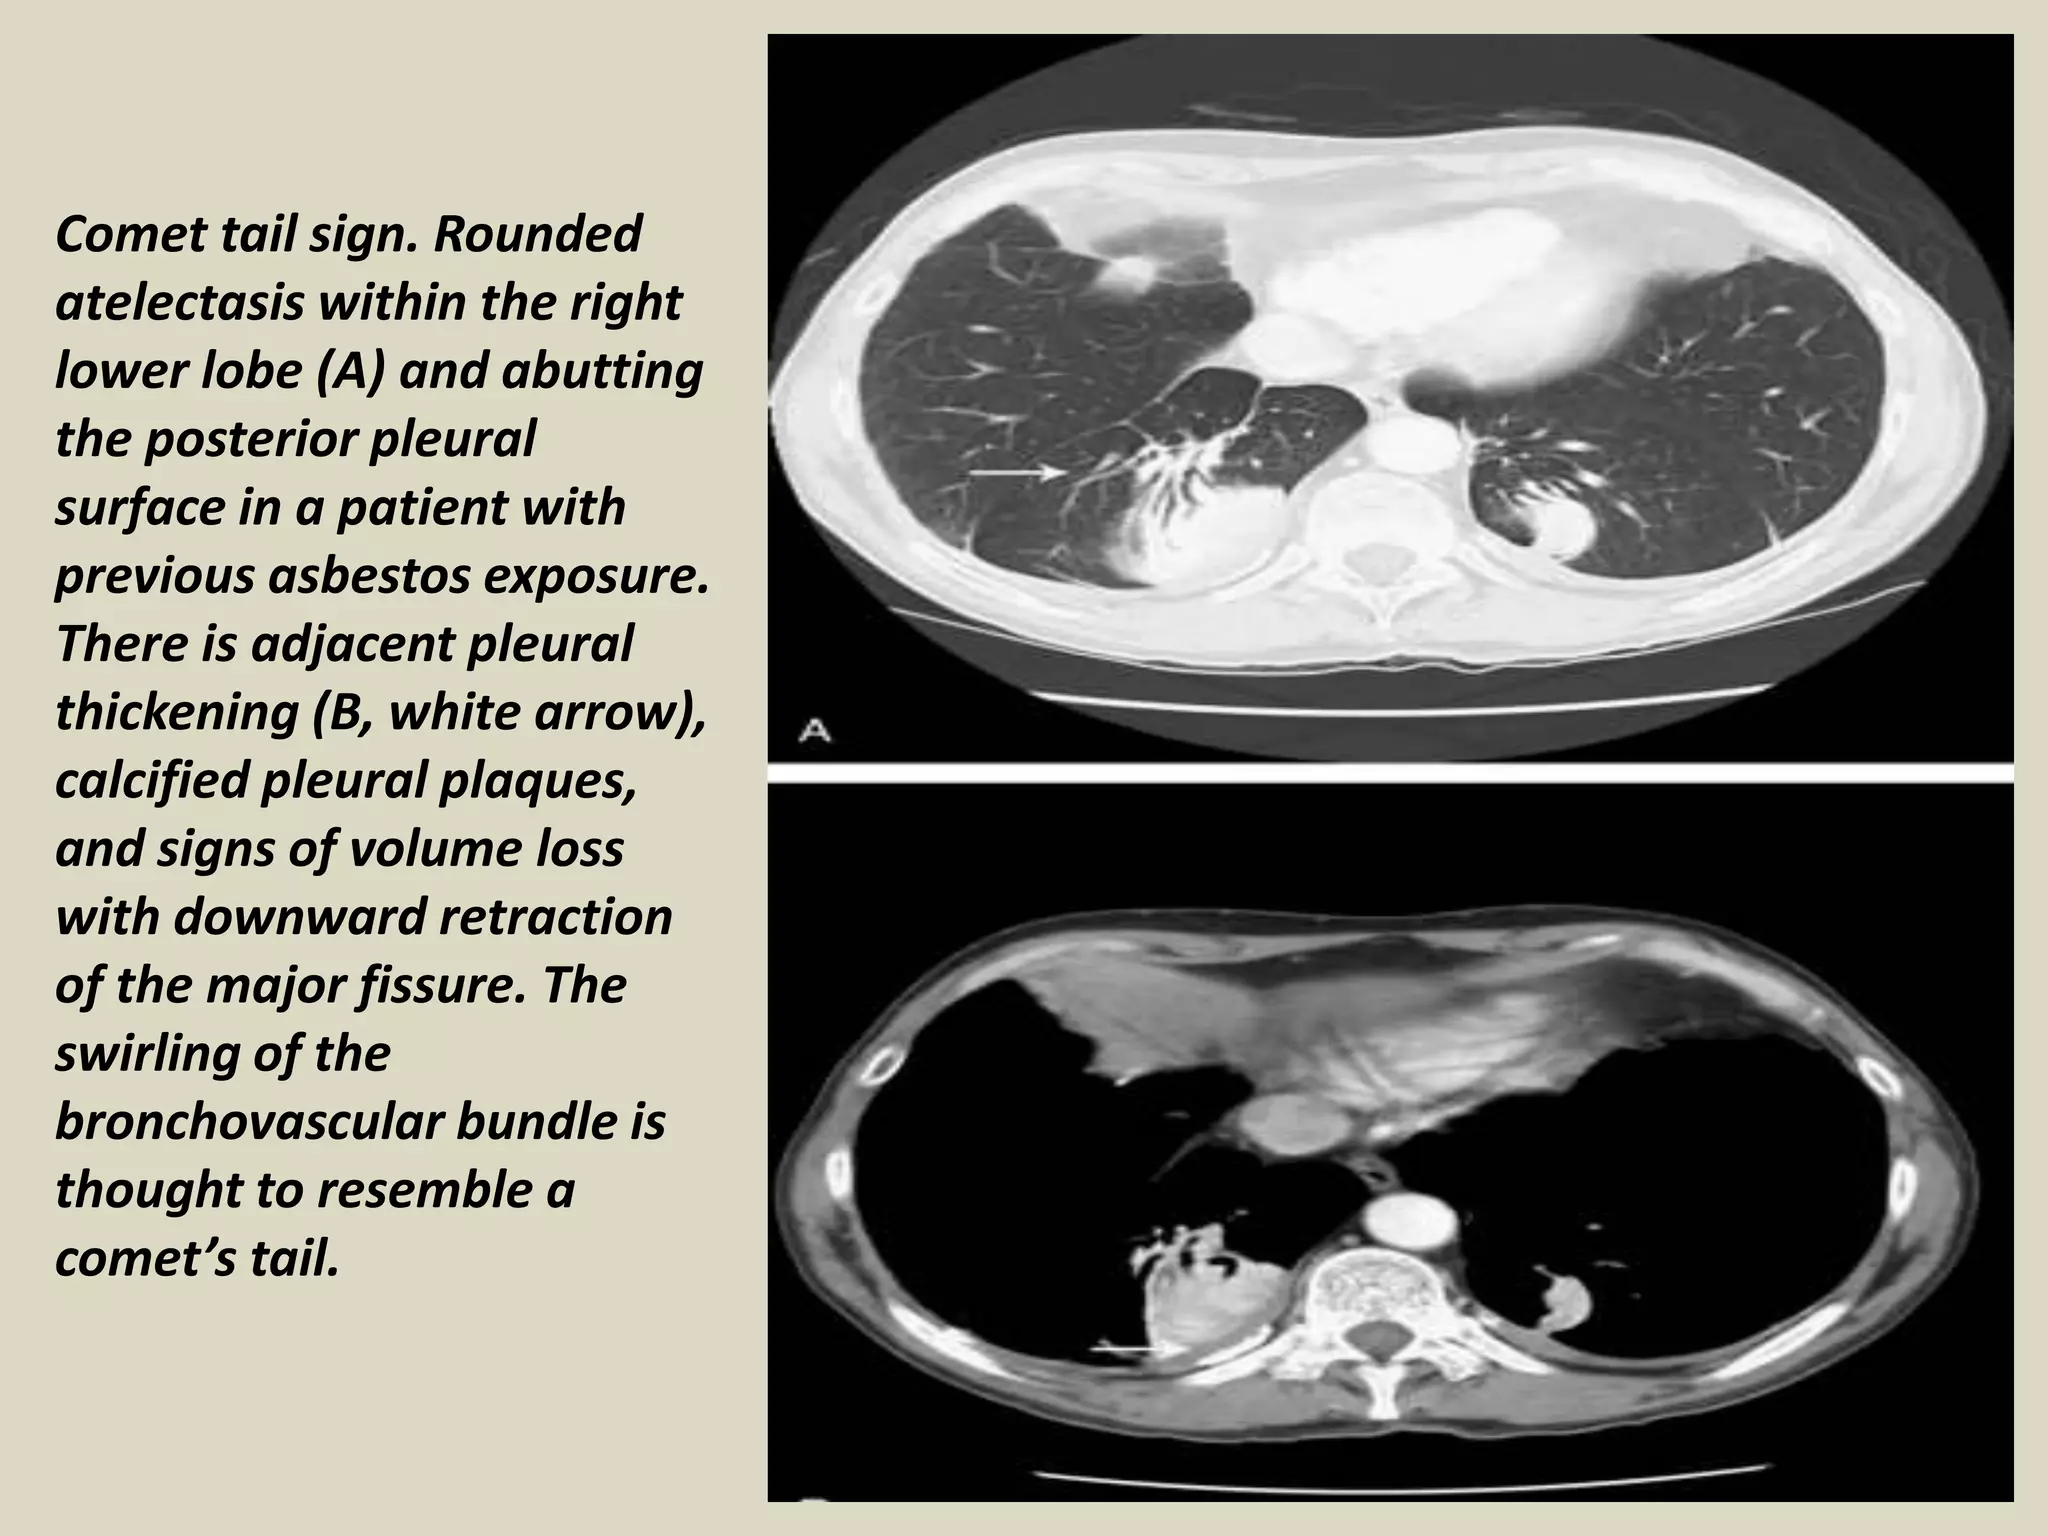

Comet Tail Sign

• Rounded atelectasis is not rare, described in patients with asbestosis

• Other conditions: CHF, Dressler, infarct, TB or parapneumonic effusions, histoplasmosis

• Round or oval opacity 2.5-8 cm, acute angles, lower lobes, enhancement

• DD includes bronchogenic Ca

Comet Tail Sign.

Comet tail sign. Rounded

atelectasis within the right

lower lobe (A) and abutting

the posterior pleural

surface in a patient with

previous asbestos exposure.

There is adjacent pleural

thickening (B, white arrow),

calcified pleural plaques,

and signs of volume loss

with downward retraction

of the major fissure. The

swirling of the

bronchovascular bundle is

thought to resemble a

comet’s tail.

Comet Tail Sign •Rounded atelectasis is not rare, described in patients with asbestosis • Other conditions: CHF, Dressler, infarct, TB or parapneumonic effusions, histoplasmosis • Round or oval opacity 2.5-8 cm, acute angles, lower lobes, enhancement • DD includes bronchogenic Ca Comet Tail Sign.

Comet tail sign.Rounded atelectasis within the right lower lobe (A) and abutting the posterior pleural surface in a patient with previous asbestos exposure. There is adjacent pleural thickening (B, white arrow), calcified pleural plaques, and signs of volume loss with downward retraction of the major fissure. The swirling of the bronchovascular bundle is thought to resemble a comet’s tail.